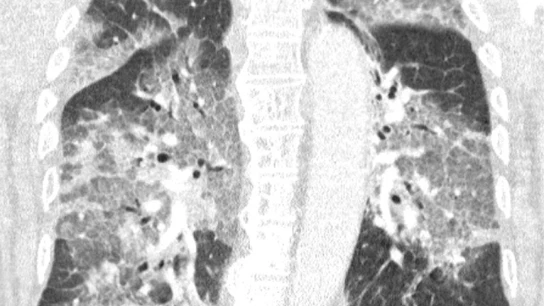

La carta abierta de estos sanitarios neerlandeses, que acompañan con una conmovedora radiografía de los pulmones del paciente, va dirigida al ministro de Sanidad en funciones, Hugo de Jonge, en una crítica a la paralización del uso de Janssen, filial de Johnson & Johnson, y de las limitaciones de edad impuestas al uso de AstraZeneca.

No es necesario ser un especialista en pulmones para reconocer la devastación"

"Ha ingresado en nuestro hospital el primer paciente que se negó a recibir la vacuna de AstraZeneca. Oímos el tremendo pesar en su voz y la desesperación en sus ojos. El virus lo ha atacado y podría haberse evitado. Con su permiso, compartimos su escáner de pulmón. No es necesario ser un especialista en pulmones para reconocer la devastación, ni epidemiólogo para explicar los riesgos de no estar vacunado", han alertado los sanitarios en el escrito.